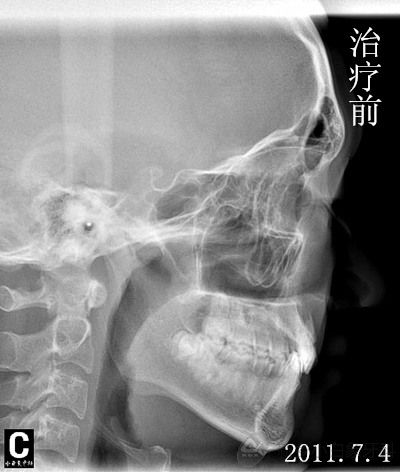

发布时间: 2014-06-27      患者李某某, 男,因“牙不齐、影响美观”来院治疗。初诊时间2011年7月4日,结束时间2014年5月1日。 接诊医生:李呈遥 患者非常满意,现将病例做一回顾性展示:

患者李某某, 男,因“牙不齐、影响美观”来院治疗。初诊时间2011年7月4日,结束时间2014年5月1日。

接诊医生:李呈遥

患者非常满意,现将病例做一回顾性展示: